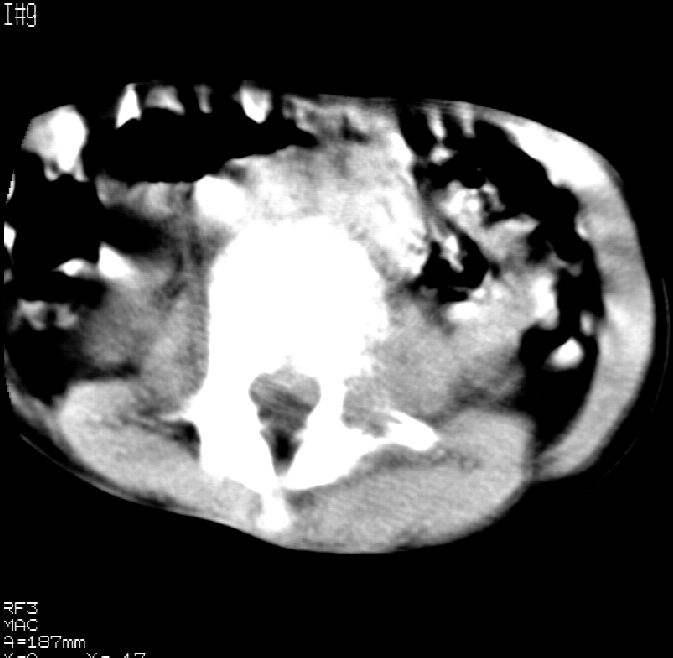

患儿女,11岁,因“腰痛,腰部活动受限10余天”入院。

10余天前,患儿无明诱因出现腰部疼痛,为持续性钝痛,以右侧为著,伴腰部活动受限,有发热,具体体温不详,无寒战、黄疸、盗汗、咳嗽,无尿频、尿急、肉眼血尿。

乍一看像是嗜酸性肉芽肿,但看到ct表现骨质破坏及软组织肿胀考虑结核可能性大,鉴别恶性肿瘤.

本例ct图像太不清楚了,而且不知道有没有传完,如果软组织病变只局限性于那几个层面的话多考虑嗜酸性肉芽肿,其次为其他肿瘤,结核椎旁软组织较广泛,在本例没有太典型表现,建议楼主(孩子父母吧)把所有的软组织窗图像(白色的那种)按顺序全部转上来.

考虑l3嗜酸性肉芽肿。